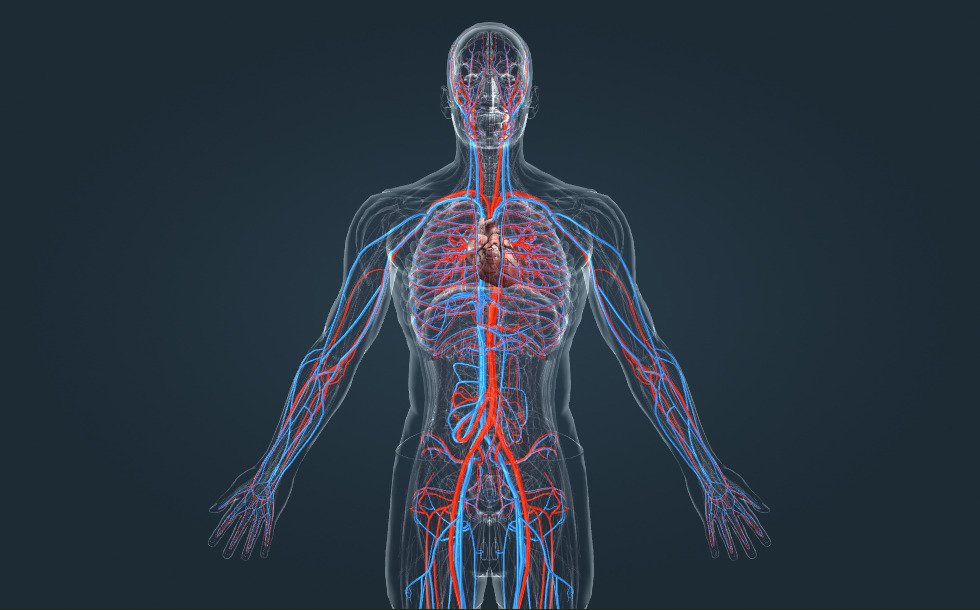

Καρδιαγγειακό σύστημα

- καρδιά - Διοχετεύει το αίμα στην πνευμονική και συστημική κυκλοφορία.

- αορτή - Η κύρια αρτηρία της συστημικής κυκλοφορίας, ξεκινάει από την αριστερή κοιλία.

Το δίκτυο αιμοφόρων αγγείων στο σώμα μας σχηματίζει το καρδιαγγειακό σύστημα. Η συστημική κυκλοφορία είναι το τμήμα του καρδιαγγειακού συστήματος που παρέχει αίμα πλούσιο σε οξυγόνο σε όλα τα όργανα του σώματος και μεταφέρει το διοξείδιο του άνθρακα. Η πνευμονική κυκλοφορία μεταφέρει το αίμα πλούσιο σε διοξείδιο του άνθρακα από την καρδιά στους πνεύμονες, όπου εκκρίνεται διοξείδιο του άνθρακα και απορροφάται οξυγόνο. Το πλούσιο σε οξυγόνο αίμα στη συνέχεια μεταφέρεται στην καρδιά. Το αίμα αντλείται μέσω των αιμοφόρων αγγείων από τις συσπάσεις της καρδιάς. Η υγεία της καρδιάς και των αιμοφόρων αγγείων διατηρείται κάνοντας τακτική άσκηση, ακολουθώντας μια υγιεινή διατροφή χαμηλή σε λιπαρά και αποφεύγοντας το κάπνισμα.

Το δίκτυο αιμοφόρων αγγείων στο σώμα μας σχηματίζει το καρδιαγγειακό σύστημα. Η συστημική κυκλοφορία είναι το τμήμα του καρδιαγγειακού συστήματος που παρέχει αίμα πλούσιο σε οξυγόνο σε όλα τα όργανα του σώματος και μεταφέρει το διοξείδιο του άνθρακα. Η πνευμονική κυκλοφορία μεταφέρει το αίμα πλούσιο σε διοξείδιο του άνθρακα από την καρδιά στους πνεύμονες, όπου εκκρίνεται διοξείδιο του άνθρακα και απορροφάται οξυγόνο. Το πλούσιο σε οξυγόνο αίμα στη συνέχεια μεταφέρεται στην καρδιά. Το αίμα αντλείται μέσω των αιμοφόρων αγγείων από τις συσπάσεις της καρδιάς. Η υγεία της καρδιάς και των αιμοφόρων αγγείων διατηρείται κάνοντας τακτική άσκηση, ακολουθώντας μια υγιεινή διατροφή χαμηλή σε λιπαρά και αποφεύγοντας το κάπνισμα.